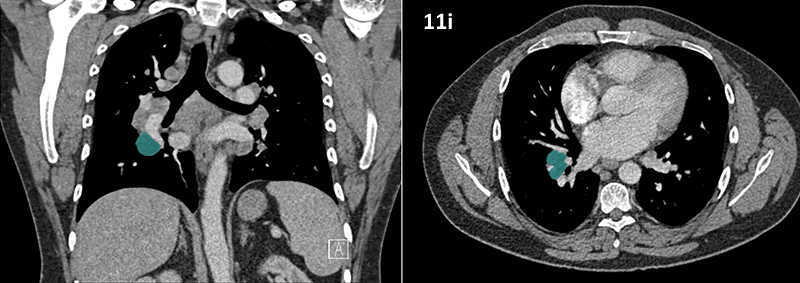

Nodal zones and stations according to the International Association for the Study of Lung Cancer (IASLC) node map.

Table (above): Nodal zones and stations according to the International Association for the Study of Lung Cancer (IASLC) node map. (Source: 1,2) *Depends on the side of the tumour.